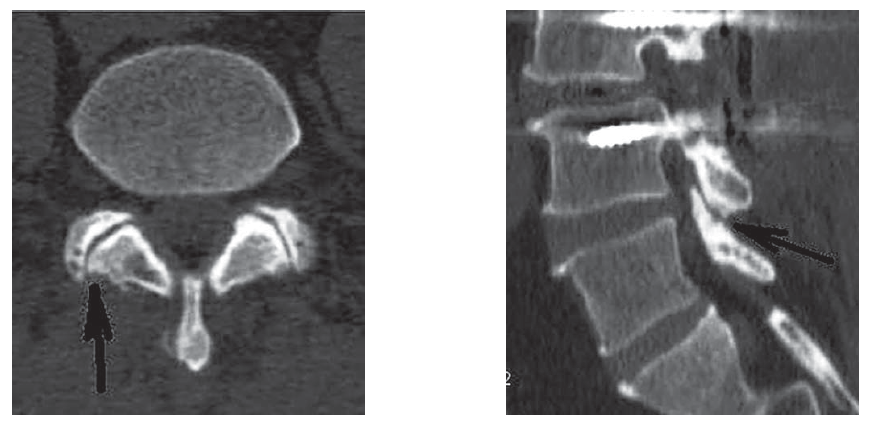

Обязательным обследованием перед процедуройВЧДМС была контрольная КТ (рис. 1).

Рис. 1. Признаки умеренных дегенеративных изменений суставов на КТ